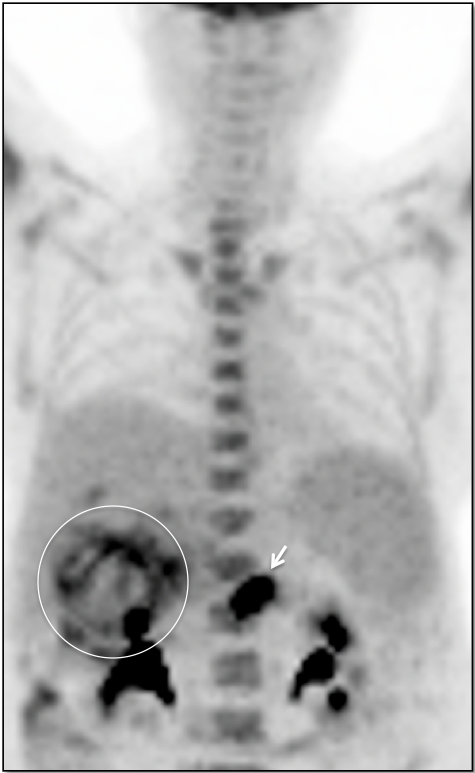

- Maximum Intensity Projection (MIP)

3. Excellent Views: The MIP, Coronal & Sagittal Images

- 3-D Rotating MIP & Coronal “Quick MIP”